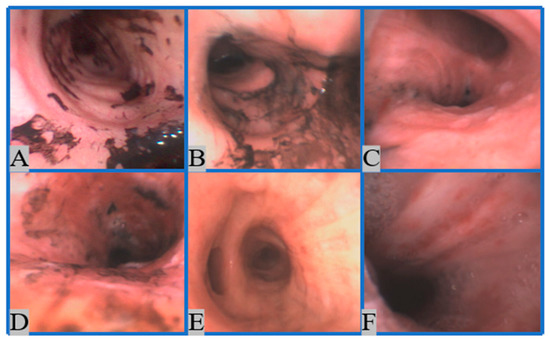

2.1. Dataset Development

2.1.1. Image Collection